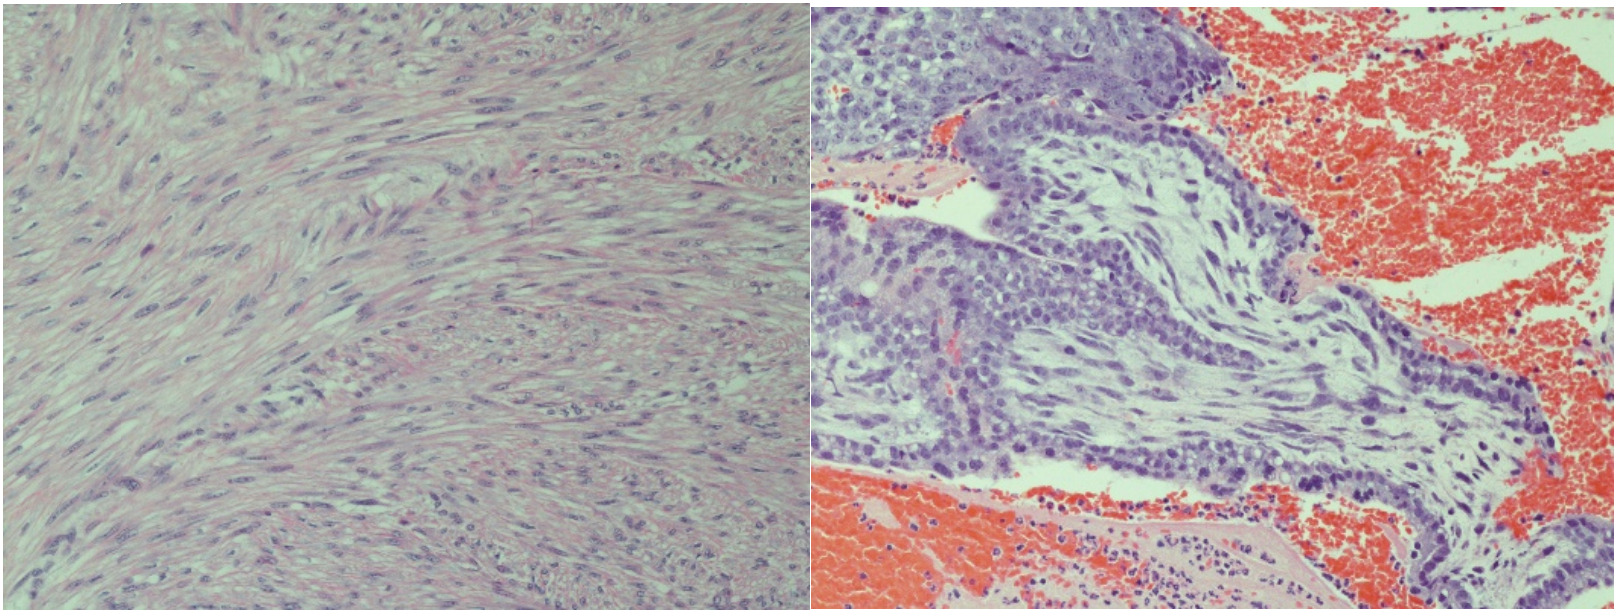

The patient was taken urgently to the operating room for diagnostic laparoscopy due to concern for right adnexal ectopic pregnancy. Upon entry into the abdomen, hemoperitoneum was noted extending into bilateral paracolic gutters. Following removal of this clot, a ruptured ectopic pregnancy was identified at the inferior pole of a 4 cm pedunculated fibroid arising from the posterior fundal surface of the uterus with active bleeding (Figure 2). This ectopic pregnancy revealed no involvement of bilateral adnexa. Pelvic survey revealed normal bilateral fallopian tubes and ovaries. The pedunculated fibroid and ectopic pregnancy were resected with the Ligasure impact device and removed from the abdomen by two separate Endocatch bags. The base of the myomectomy (Figure 3) was oversewn with 2-0 vicryl for additional hemostasis.

The patient had an uncomplicated postoperative course and was meeting all expected postoperative milestones at her 6 week follow-up. Surgical pathology confirmed diagnosis with visualized rare immature chorionic villi and syncytiotrophblasts, consistent with products of conception and leiomyoma. Her β human chorionic gonadotropin was followed to a negative value (2.7 mIU/mL) which occurred at 2 weeks postoperatively.